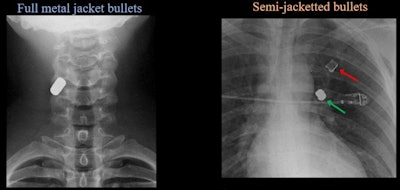

Several images illustrated the difference in impact between full metal jacket bullets versus semi-jacketed bullets.